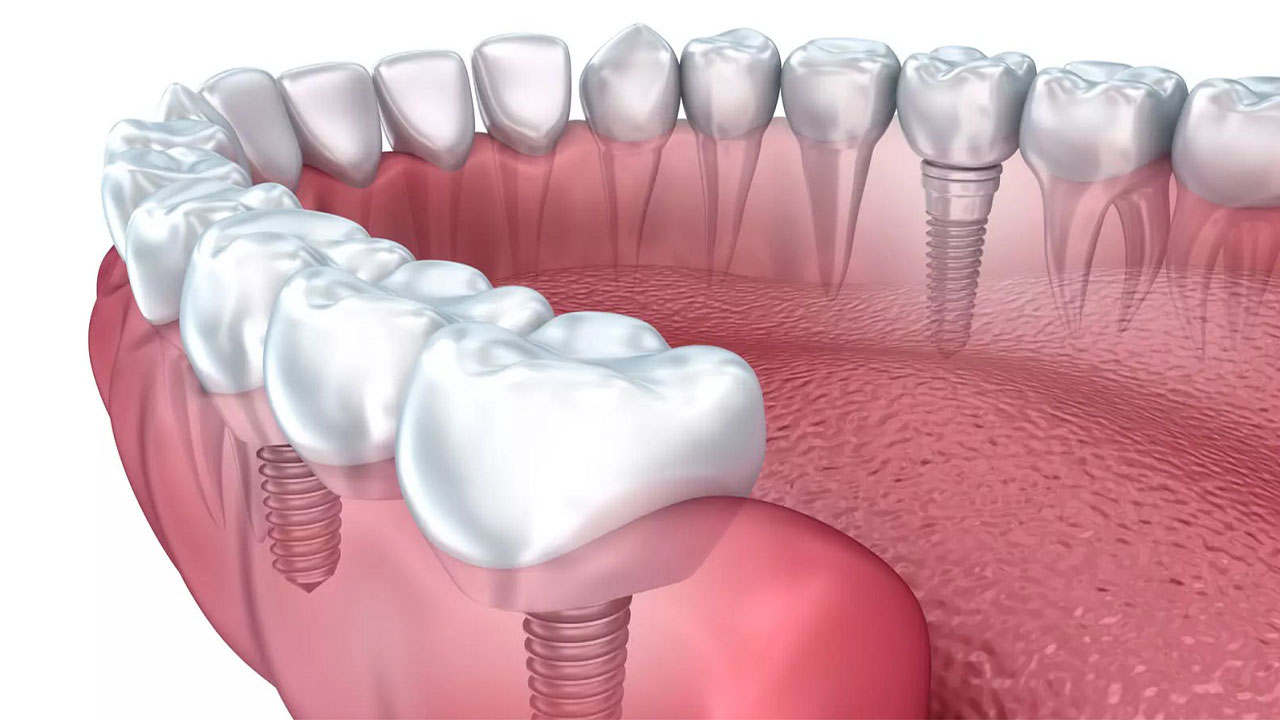

ایمپلنت دندان

بهترین جایگزین برای پر کردن جای خالی دندان از دست رفته ایمپلنت است. ایمپلنت دندان از جنس تیتانیوم بوده و به صورت میله باریکی است که درون استخوان فک قرار می گیرد. فلز تیتانیوم به کار برده شده در این روش درمانی، با بدن سازگار بوده و مشکلی را به وجود نمی آورد. اگر پس از قرار گرفتن در فک به صورت صحیح از آن مراقبت شود، ماندگاری بالایی خواهد داشت دارد. در نهایت اگر یک یا بیش از یک دندان خود را از دست داده اید، در این صورت بهترین روش برای اصلاح طرح لبخند یا زیباسازی لبخند، قطعا کاشت ایمپلنت دندان است.